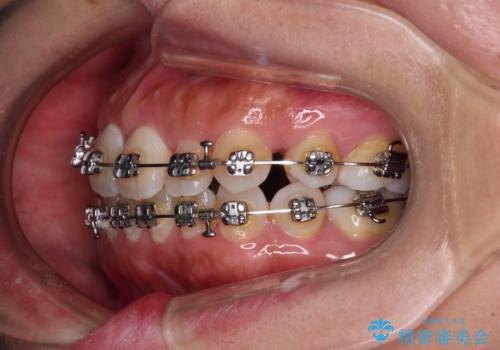

既に2本が抜歯されている歯列 咬み合わせのズレを改善する抜歯矯正

- 上下前歯のデコボコを気にして来院された患者様です。

右上と左下の小臼歯が1本ずつ欠損しており、奥歯の咬み合わせが乱れている状態でした。

バランスを取るために右下と左上の小臼歯を1本ずつ抜歯し、移動のための固定源としてアンカースクリューを利用してワイヤー装置による矯正治療を行うこととしました。

骨格的な左右差があり、上下正中をぴったり合わせることは難しく、奥歯の咬み合わせの調整にも時間がかかりましたが、きれいに整えることができました。